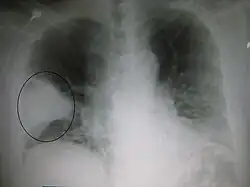

Enfermedades del pulmón

- Cáncer de pulmón: Es una de las enfermedades pulmonares más graves y uno de los cánceres con mayor incidencia en el ser humano. En función de la apariencia de las células cancerosas, puede distinguirse entre cáncer de pulmón microcrítico y cáncer de pulmón no microcrítico. El primero recibe también el nombre de cáncer de células en grano de avena, su nivel de incidencia representa entre un 10 y un 15 % del total de cánceres de pulmón diagnosticados. El no microcítico se divide, a su vez, en adenocarcinoma, carcinoma de células escamosas y carcinoma de células grandes. Otros tipos de tumores malignos en los pulmones son los tumores carcinoides, linfomas y sarcomas. El tabaco es el factor de riesgo más importante a la hora de sufrir un cáncer de pulmón, motivando hasta un 80 % de las muertes por esta enfermedad.[12]

- Tuberculosis: Se trata de una enfermedad infecto-contagiosa que se suele contagiar por vía aérea, está provocada por el mycobacterium tuberculosis.